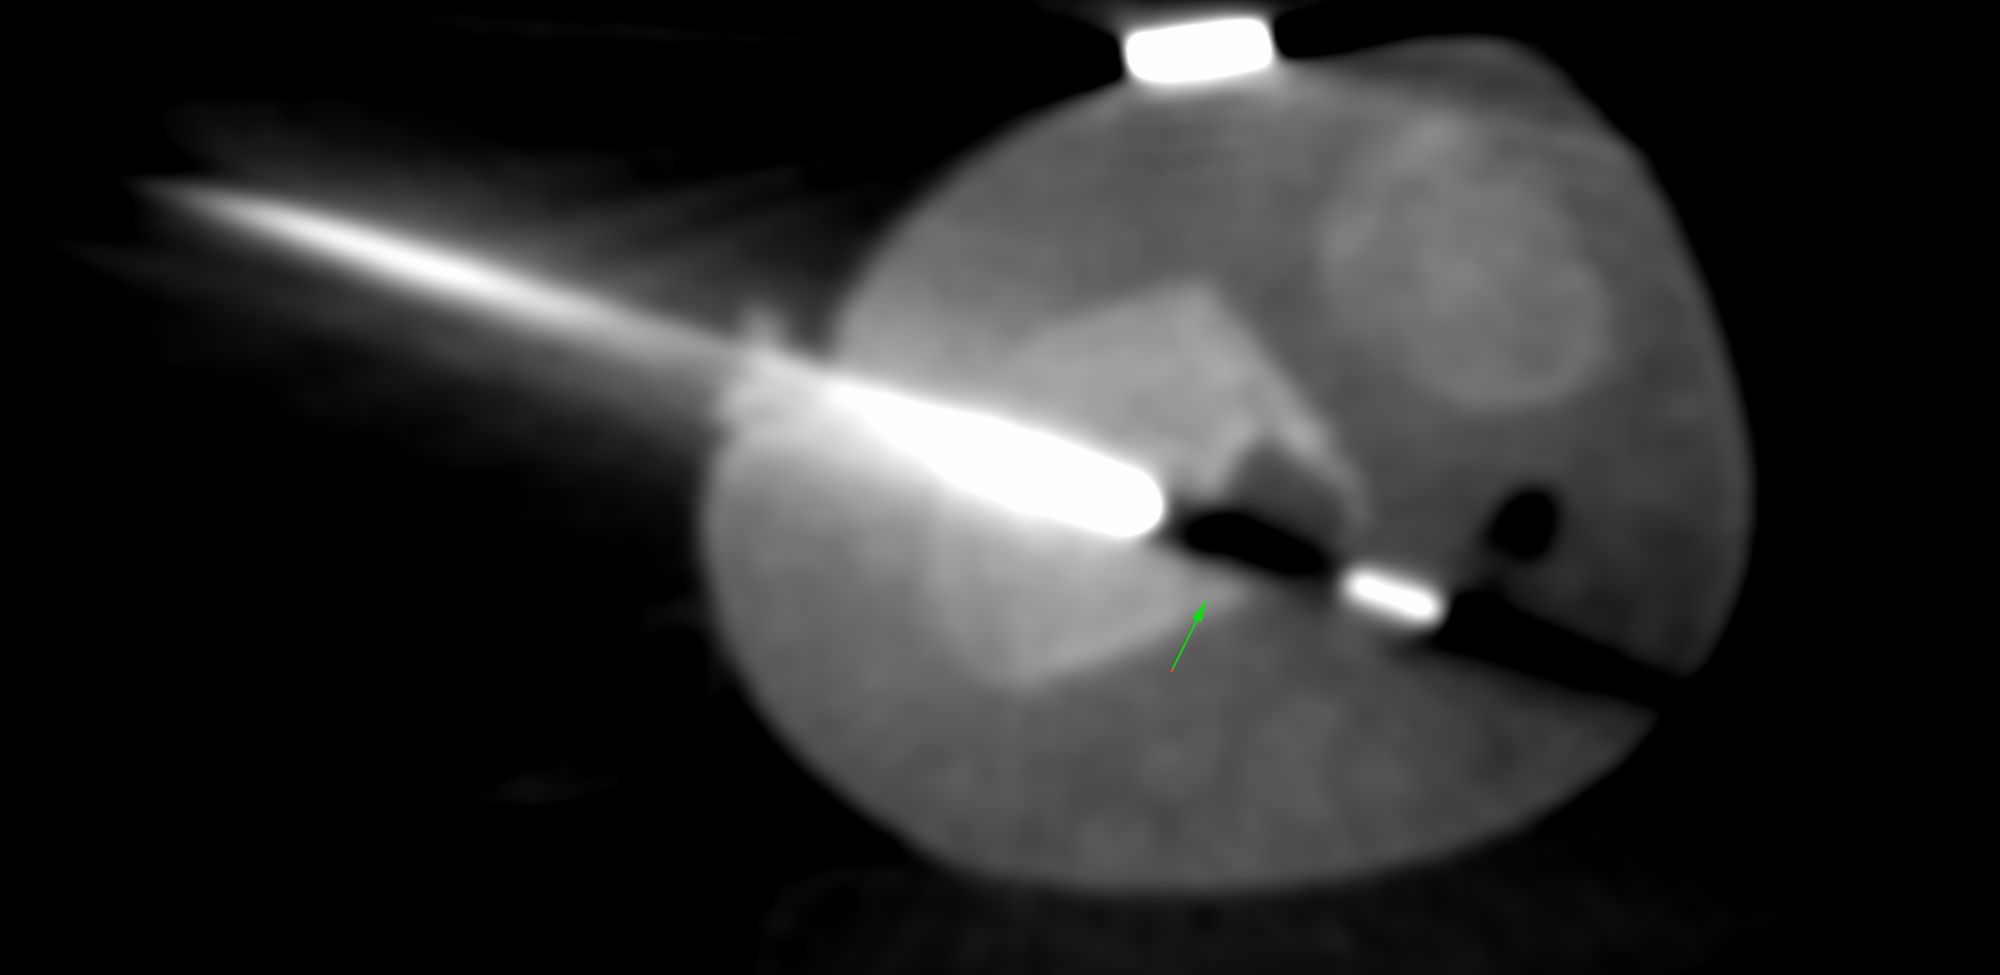

Case 9: Pediatric Distal Radius Lesion Biopsy